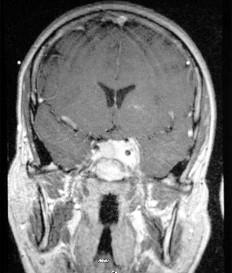

问题 有关脑膜瘤(如图所示),下列哪项说法不恰当()

选项 A.脑膜瘤发病率居颅内肿瘤的第二位 B.一般男女发病率之比约为1:2 C.多数脑膜瘤为良性肿瘤,但有少数脑膜瘤在病程中发生恶性变 D.脑膜瘤多发源于软脑膜细胞 E.多发生于旁矢状面和凸面

答案 D